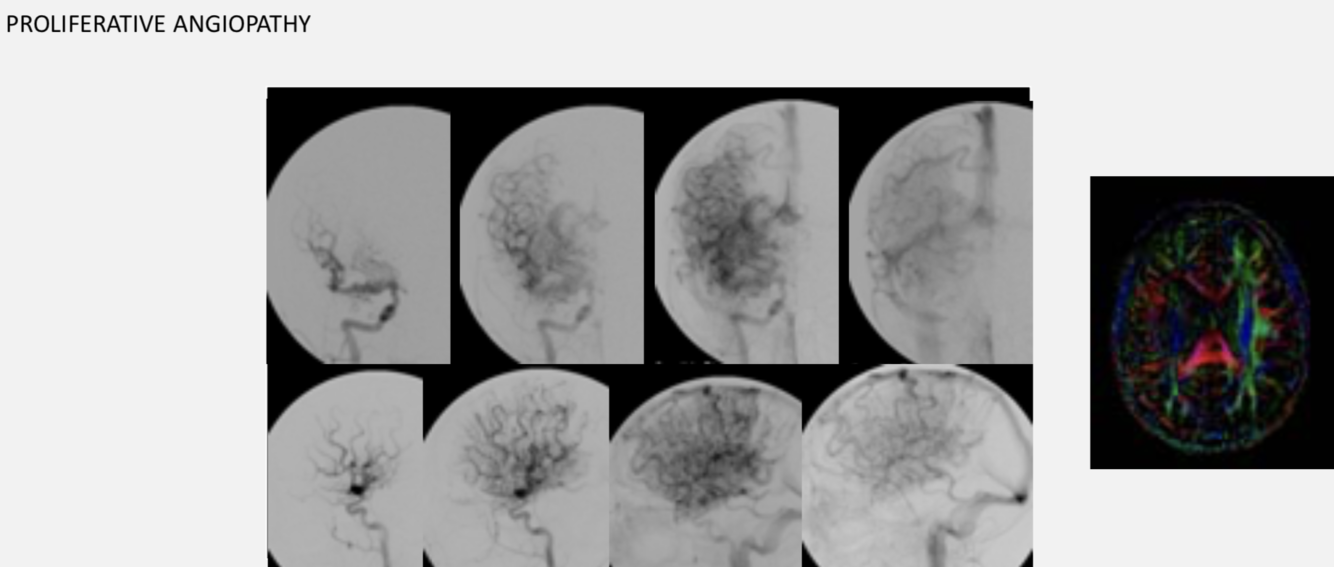

AVM - ddx

.